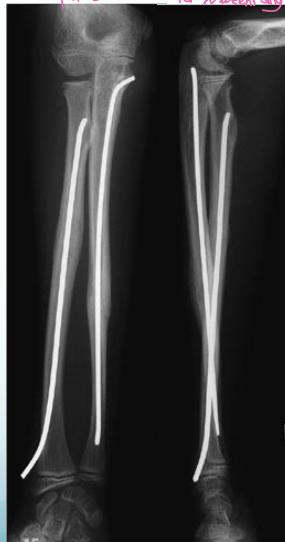

Elastic Intramedullary Nails

- For unstable fractures – minimal surgery

- Put back slab for 2 weeks only